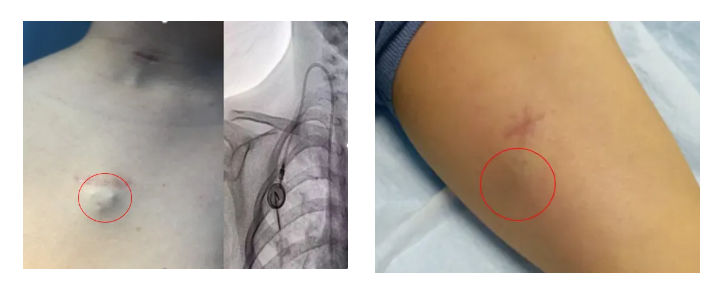

輸液港,即完全植入式輸液港(PORT),是一種可完全植入皮下并長期留存體內(nèi)的輸液裝置,主要由注射座(又稱港體)和硅膠導(dǎo)管兩部分組成。注射座被埋植于胸部皮下,導(dǎo)管則連接到上腔靜脈,形成一個閉合的靜脈輸液系統(tǒng)。其常見類型有手臂輸液港與胸壁輸液港。

提高生活質(zhì)量:輸液港埋植體內(nèi),外觀無外漏導(dǎo)管,患者可自由活動。